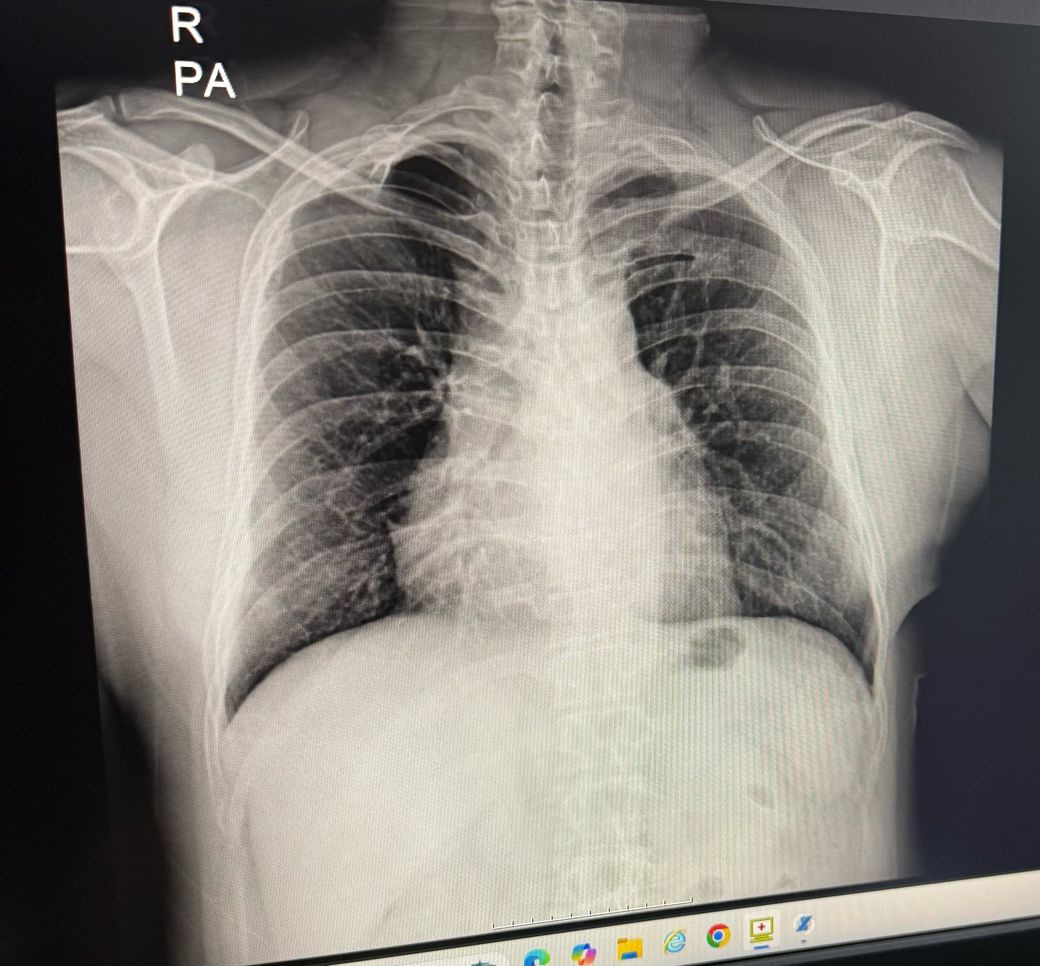

오른쪽 어깨 맨위쪽에 뼈가 하나 있습니다.

이걸가지고 경추늑골이라고 하던데 골종양병원이라든지 대학병원에가서 진료를 봐야할까요?

30대 중반 남자이고 아픈사항은 없습니다. 살면서 오른쪽어깨 부위 크게 아픈적없습니다.

• 사진 기준으로 보이면

많은 경우 정상적인 쇄골·견봉(어깨뼈) 윤곽이 튀어나와 보이는 것이거나, 상부 늑골의 변형, 근육·지방층 차이 때문에 도드라져 보이는 정도가 흔합니다. 말씀하신 ‘경추늑골(cervical rib)’은 실제로는 드물고, 대부분 우연히 X-ray에서 발견됩니다.